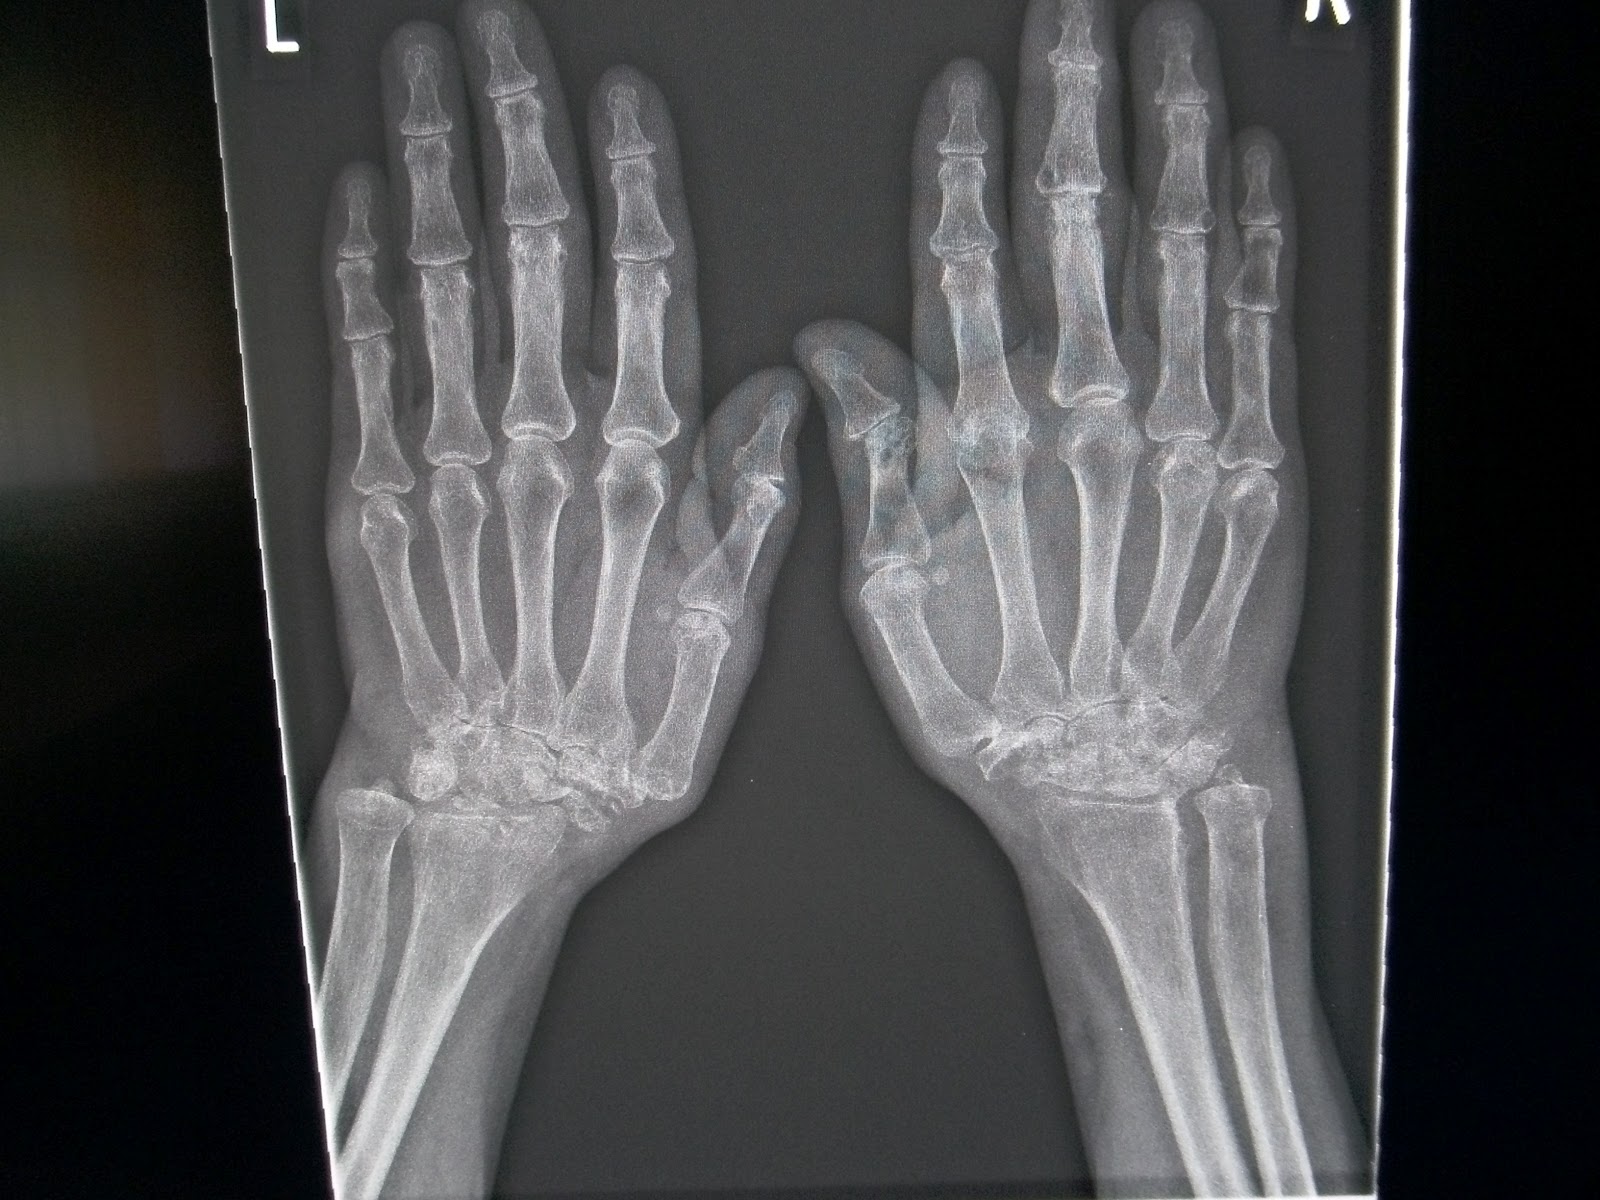

Rheumatoid Arthritis Hands X Ray What Does Ra Stand For In Radiology Various imaging modalities help the radiologist and the rheumatologist in making an early diagnosis of. Imaging findings in rheumatoid arthritis (ra) reflect the pathophysiology of the disease. Rheumatoid arthritis (ra) is a chronic autoimmune multisystemic inflammatory disease that affects many organs but predominantly attacks the synovial tissues. Rheumatoid arthritis (ra) imaging tests are used to look for signs of ra. What Does Ra Stand For In Radiology.

Rheumatoid arthritis hands Radiology at St. Vincent's University What Does Ra Stand For In Radiology Various imaging modalities help the radiologist and the rheumatologist in making an early diagnosis of. Learn what types of imaging scans are most effective in detecting and monitoring ra. Ra in radiology commonly refers to radiologist assistant, a healthcare professional who assists. Imaging tests for rheumatoid arthritis. Rheumatoid arthritis (ra) is a chronic multisystem disease with predominant musculoskeletal manifestations. The. What Does Ra Stand For In Radiology.